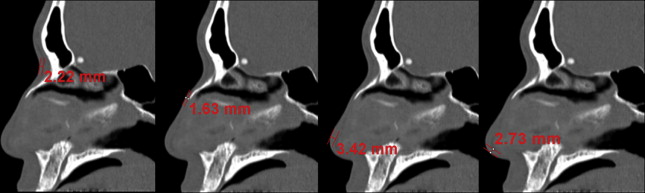

The tip of the Asian nose, particularly the east Asian or oriental nose, is usually low, and the lower lateral cartilages are small and weak. The nasal bones are flat and thick, resulting in a low radix. The average nasal length/nasal tip projection/dorsal height/radix height ratio of the nose in white people has been shown to be 2:1:1:0.75 ( Fig. 1 A). However, in the senior author’s study, young Koreans had a nasal length/nasal tip projection/dorsal height/radix height ratio of 2:0.97:0.61:0.28 (see Fig. 1 B). This finding supports the popularity of augmentation rhinoplasty to correct a low-profile nose among Asian people. Regarding the septum, the septal cartilage of some Asian people is thin and small. In a study of the senior author’s patients having external rhinoplasty, intraoperative measurement of the harvested septal cartilage was performed with preservation of L struts 10 mm wide. The mean caudal length of the harvested septal cartilage was 15.1 mm, and the mean dorsal length was 18.2 mm. Therefore, the size and the quantity of harvestable septal cartilage may be inadequate for complex rhinoplasty procedures, increasing the need of harvesting grafts from other sites. Typical Asian noses tend to have thicker skin than noses of white people, with abundant subcutaneous soft tissue. In the senior author’s research using computed tomography (CT) scans of the nose of Koreans, the mean nasal skin thickness was 3.3 mm at the nasion, 2.4 mm at the rhinion, 2.9 mm for the nasal tip, and 2.3 mm for the columella ( Fig. 2 ). In this study, the thick skin at the nasal tip and columella was associated with poorer surgical outcomes, suggesting that regional skin thickness is an important prognostic factor for tip surgery success.